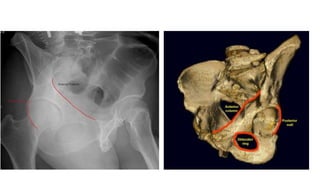

● Anatomy

○ Supported by two columns

○ Anterior column

■ Anterior ilium,anterior wall and dome, iliopectineal eminence, superior pubic rami

○ Posterior column

■ Quadrilateral plate, posterior wall and dome, ischial tuberosity, greater and lesser sciatic

notch

● Anatomy ○ Acetabularcap ■ 40-48 deg lateral inclination , 18-21 degree anteversion ○ Supported by two columns ○ Anterior column ■ Anterior ilium,anterior wall and dome, iliopectineal eminence, superior pubic rami ○ Posterior column ■ Quadrilateral plate, posterior wall and dome, ischial tuberosity, greater and lesser sciatic notch